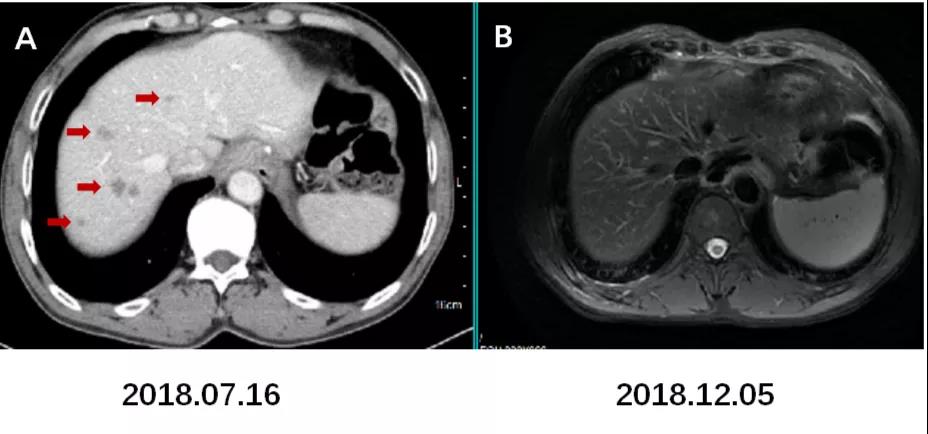

肝脏磁共振增强扫描(2018.12.05):原增强CT提示肝脏转移瘤区域未见明显病灶。

strong>图9. 肝脏转移灶未见复发。

A:术后CT增强(2018.07.16)示肝脏多发转移灶。B:术后MRI增强(2018.12.05)示肝脏转移灶消退后未见明显复发病灶。

图10. 左肾上腺区、膈下及腹膜后淋巴结较前退缩。

术后CT增强C1(2019.03.12)示左肾上腺区转移灶较前片A1(2018.07.16)以及B1(2018.11.03)明显退缩;C2,C3示膈下及腹膜后淋巴结前片也明显退缩。影像评估CR。

(3)疗效评价:CR。